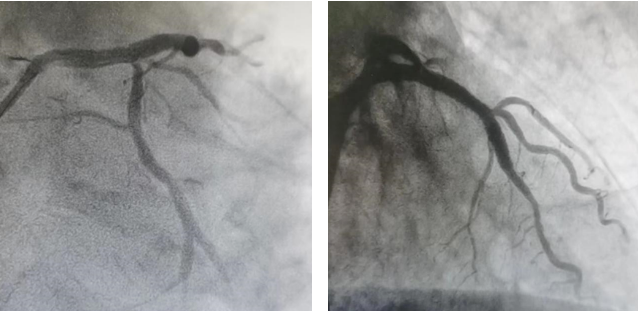

造影结果

LM:远段狭窄80%。

LAD:斑块浸润,开口及近段弥漫狭窄70-95%。

LCX:开口约狭窄70%,高位OM开口狭窄90%。

RCA:斑块浸润,远端狭窄50%。

▲ 最后造影结果理想满意